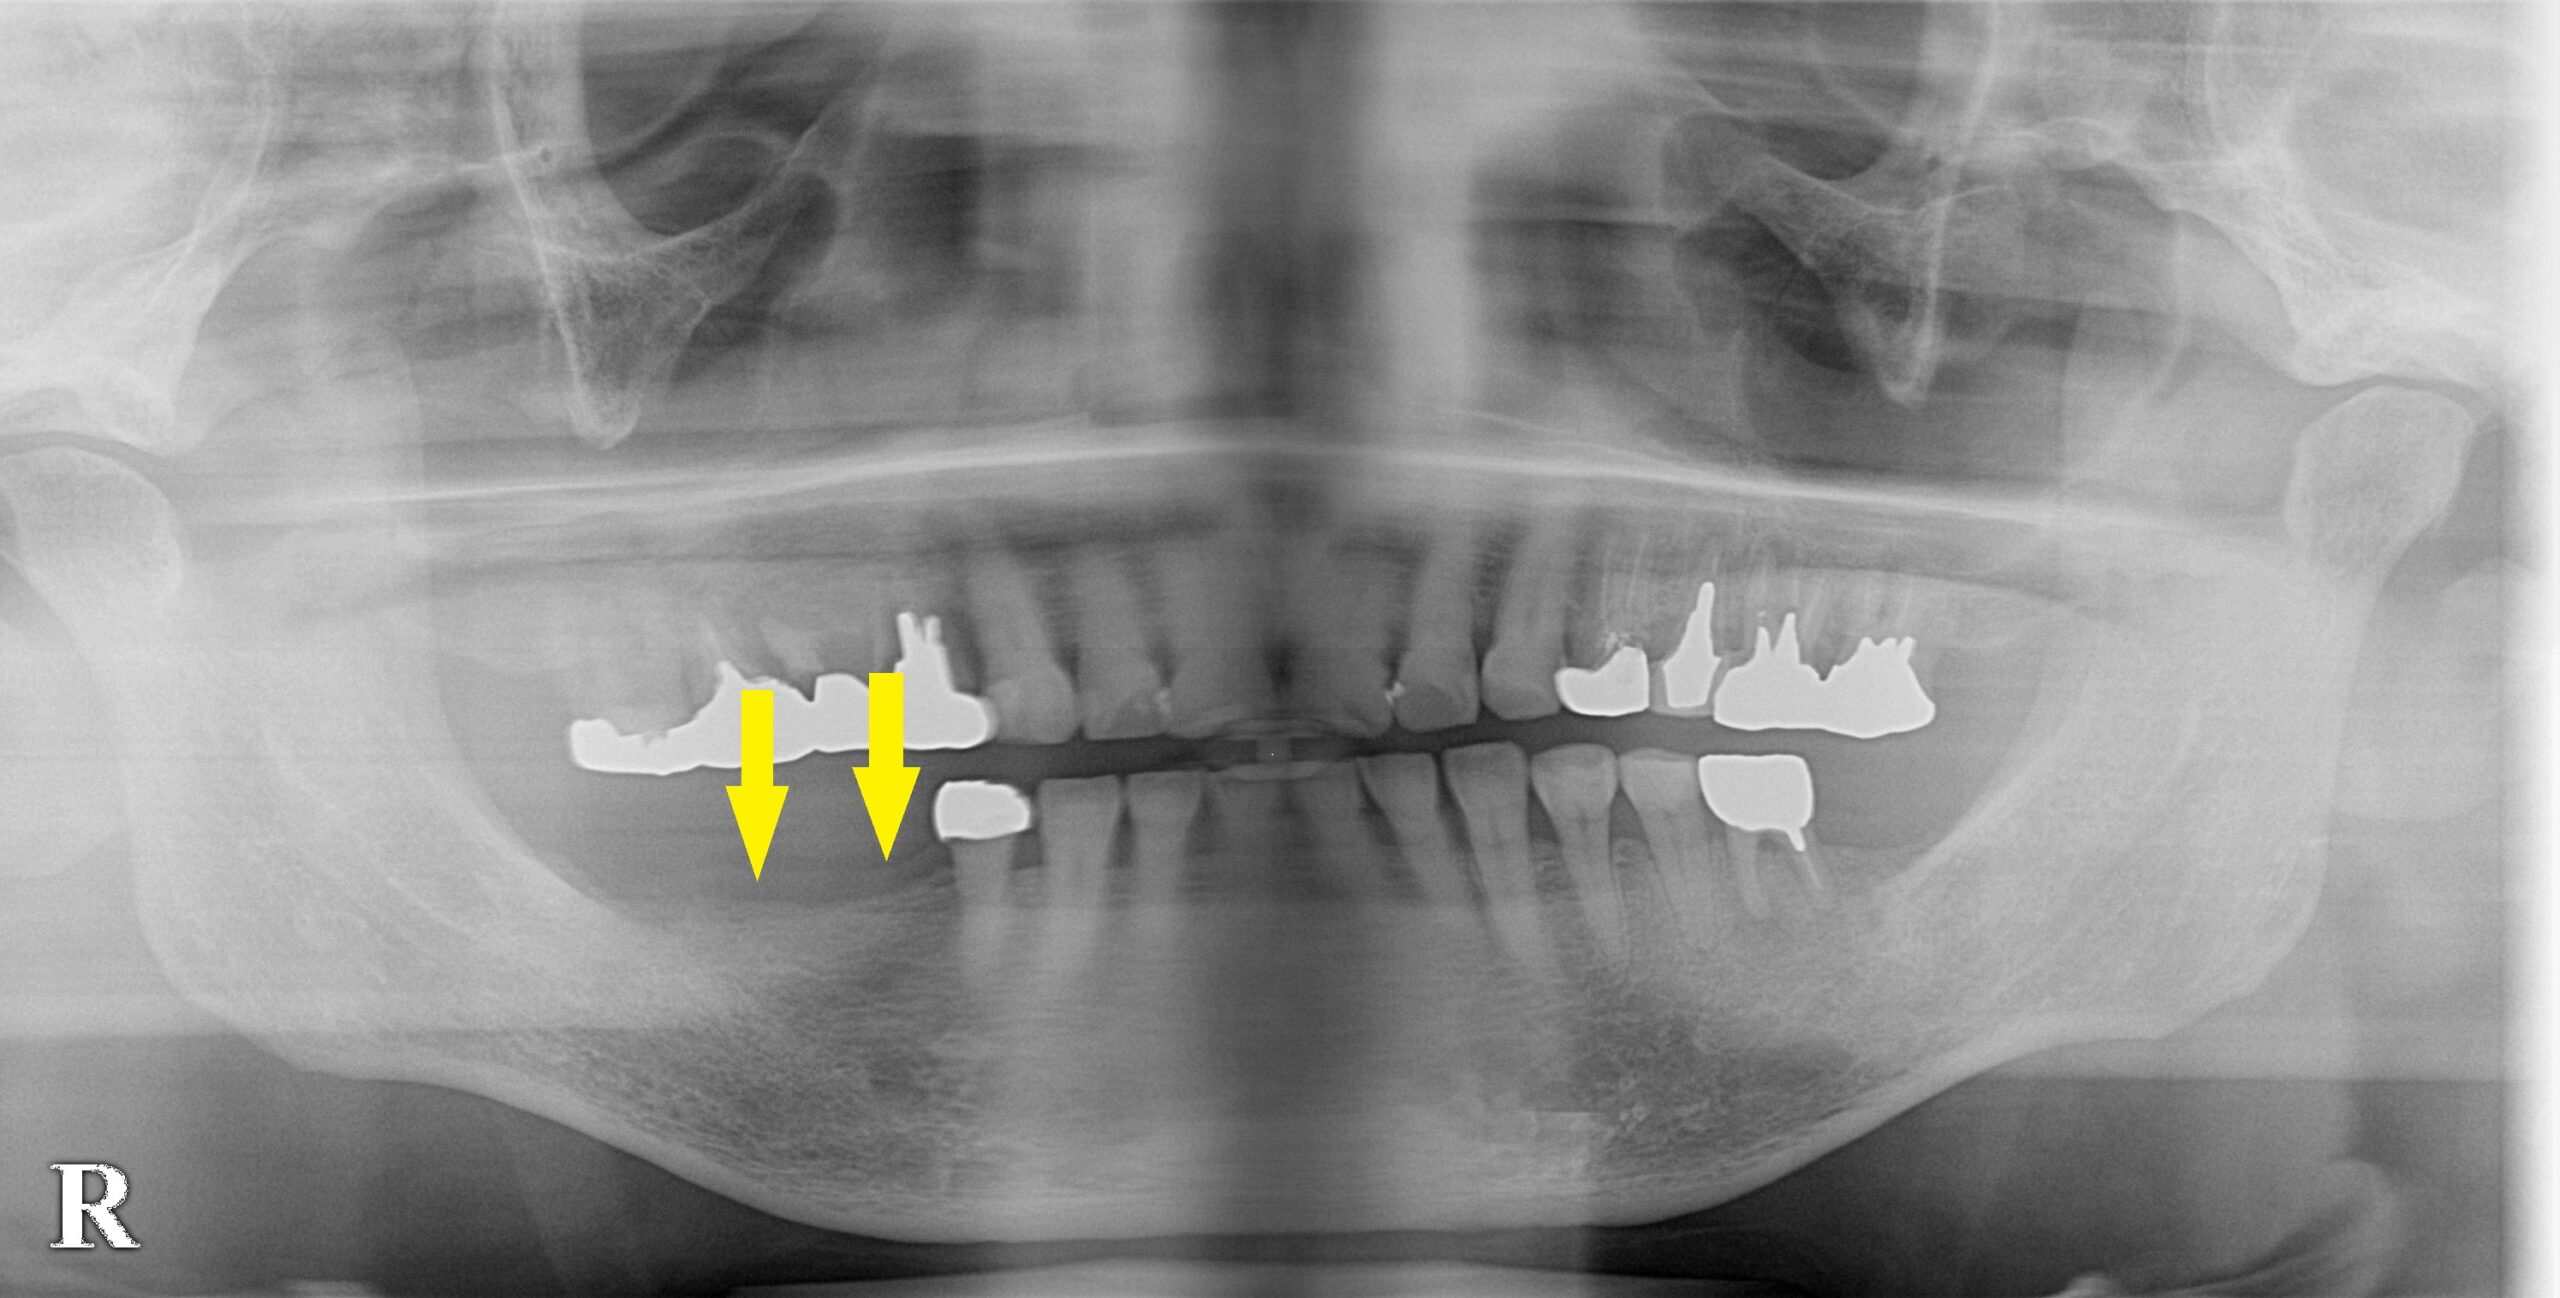

患者様は名古屋在住の60代女性。

右下顎の臼歯のインプラント治療を希望されて、来院されました。

お口の中を拝見すると、歯肉がやせて細くなってしまっている状態でした。

CTで見ると、歯肉がやせているのと同じように、骨も細くなってしまっていました(下の写真2段目)。

骨幅が狭いので、インプラント埋入と同時に、外側に人工骨を補填して、骨幅を増やす、骨造成術の併用が必要であると説明させていただきました。

ご了承いただけましたので、本日、2本のインプラント埋入と、骨造成術を行いました。

下顎大臼歯と小臼歯の骨造成症例

今週のインプラント症例